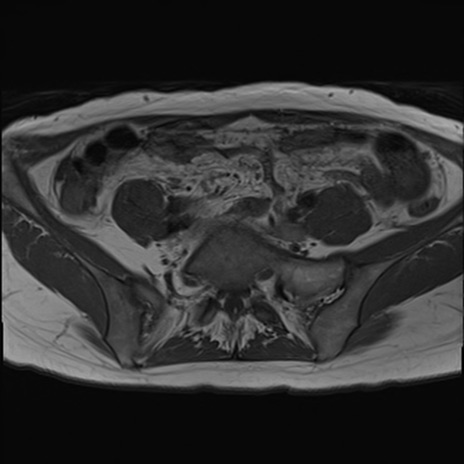

症例39 T1WI(横断像)

【症例】40歳代女性

【主訴】上下腹部痛

【現病歴】2日目から下腹部痛あり。夜間は痛みで眠れなかった。昨日より上腹部痛と下痢が出現。臥位で痛みは軽快したため、休んでいた。本日になって臥位でも立位でも痛みが強くなってきたため救急要請。

【既往歴】子宮内膜症

【身体所見】部:平坦・軟、左上下腹部に圧痛あり、反跳痛あり。

【データ】WBC 21800、CRP 26.78

MRI(4日後)